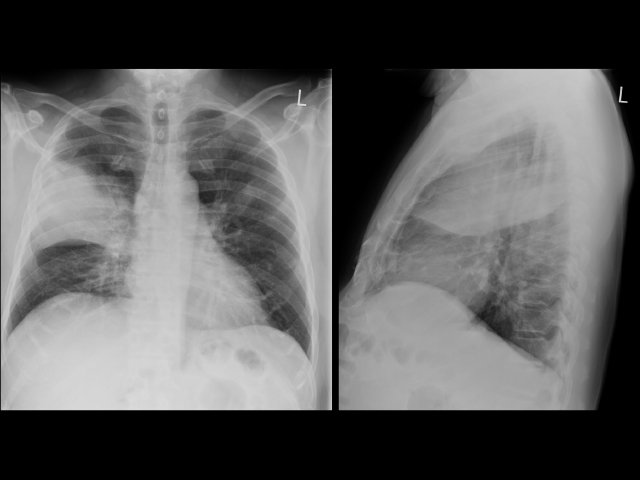

52 minutes Chest X-Ray Recorded on 27th Jan 2016 In this webinar, we’ll go over several interesting chest x-ray cases. We’ll cover things you might encounter during your next night on call.